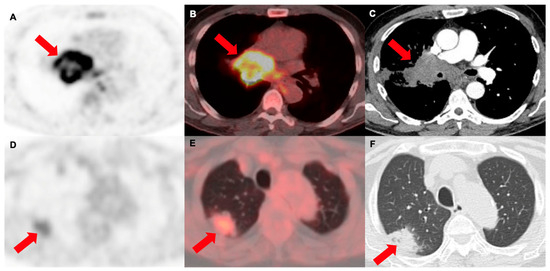

3.3. Prediction of Histology and Anatomical Disease Origin